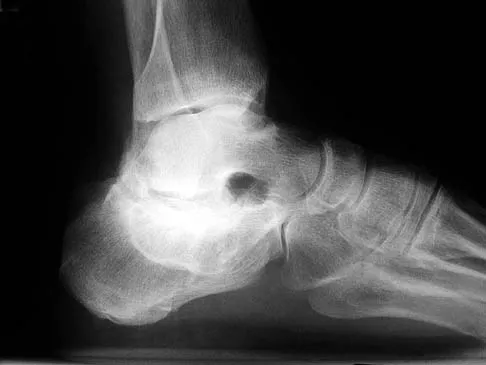

Figure 7 shows the CT scan of a 25-year-old soccer player who has had posterior ankle pain with plantar flexion for the past 2 years. Immobilization has failed to provide relief. He is ambulatory. Management should consist of

Explanation

An os trigonum is usually asymptomatic, but this accessory bone has been associated with persistent posterior ankle pain, which has been described as os trigonum syndrome. This usually affects athletes and ballerinas. Forced plantar flexion leads to impingement of the os trigonum against the posterior tibial plafond, and flexor hallucis tendinitis may develop. It may be difficult to differentiate a fractured trigonal process from the os trigonum. MRI may reveal bone marrow edema that may aid in the diagnosis of os trigonum syndrome. Steroid injections may lead to tendon rupture. The results of excision of a symptomatic os trigonum through a posteromedial or lateral approach are favorable, with a rapid return to full function. The main complication of this procedure is sural nerve injury with a lateral approach. Hedrick MR, McBryde AM: Posterior ankle impingement. Foot Ankle Int 1994;15:2-8.